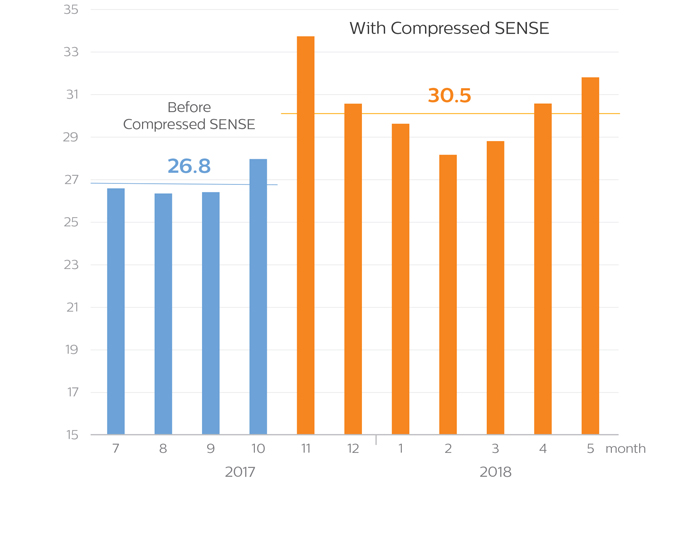

“In September and October our average number of patients per day was about 27 on Ingenia 3.0T CX. We started using Compressed SENSE in November and we completed that month with scanning an average of more than 33 patients per day. That is 6 more patients per day than in September and October!”

A higher average number of patients scanned per day

in each month after KNC started using Compressed SENSE

Average number of examinations per day

This 11-month diagram shows that the average number of patient examinations per day on the Ingenia 3.0T CX has increased since Compressed SENSE is used. Although the highest throughput was achieved in the first month of using Compressed SENSE, the graphs demonstrate the realization of higher throughput of 14% on average over a longer term.

Average number of examinations per day (9:00 - 18:00)

In order to exclude the effect of overtime, the daily average number of patients scanned between 9:00 and 18:00 h was also calculated. It confirms that on average three additional patients per day were scanned since implementation of Compressed SENSE.